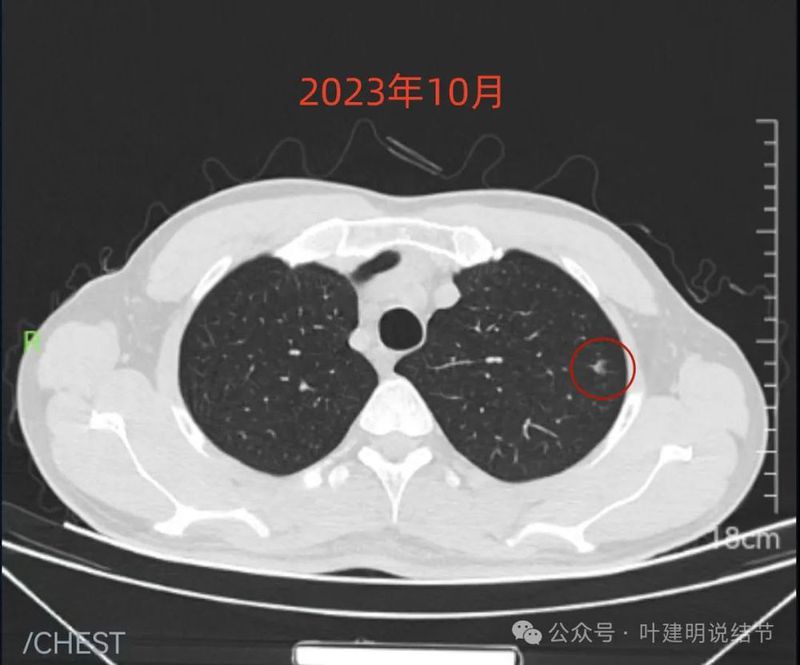

先看不同时间的明显层面截图:

2023年10月时右侧病灶没有明显进展。

2023年10月时左侧病灶较前略明显,便仍觉得密度从高到低有移行,由于整体轮廓较前明显,恶性的可能性增加了。

2024年3月右侧病灶仍无明显两样。

2024年3月时左上病灶感觉密度更高了点。